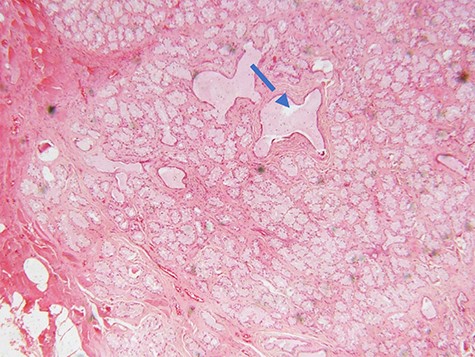

Microscopic examination of the excisional biopsy materials showed a lesion composed of proliferating acinar (Fig. 1) with lining epithelium composed of columnar to cuboidal mucin-secreting cells showing no atypia (Fig. 2). The lesion was divided by fibrous septae to form lobules (Fig. 3). There was a focal area that was showing element of moderate dysplastic changes with element of obliterating tubules, increased hyperchromasia and moderate pleomorphism (Fig. 4). The ratio of duct-to-acini was maintained. Sparse chronic inflammatory infiltrate composed of mainly lymphocytes was present. Neither mitoses nor necrosis were present. The surgical margins were free of the lesion. This confirmed the histopathological diagnosis of Bartholin’s gland hyperplasia with dysplastic changes. After a period of 1 month she was called for clinical evaluation. Healing of the surgical scar was complete and she reported no discomfort or dyspareunia during sexual intercourse.

photomicrograph of haematoxylin and eosin (H and E) stained tissue section showing a lesion divided into lobules by fibrous septae in which proliferating and congested blood vessels are seen. The typical columnar to cuboidal mucin-producing epithelial cells are basally located with abundant pale cytoplasm (arrow) (×100 magnification)